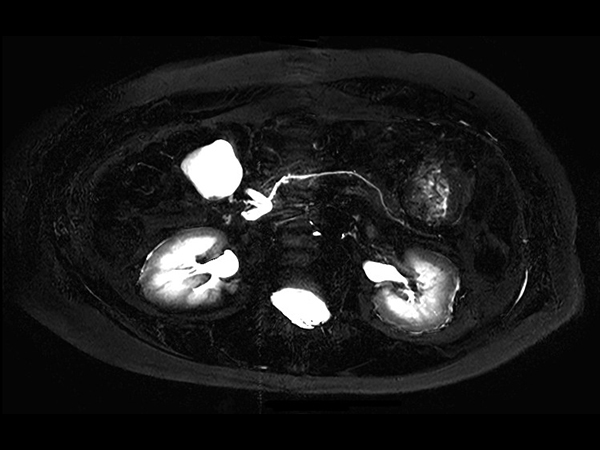

Axial MRCP 2D